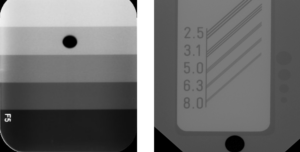

Strålehygiejne i top – øvelser i variation af eksponeringsværdier (caries el. apex)

Rektangulær tubus & optagelsesteknikker – lær at bruge rektangulær tubus korrekt og anvende receptorholdere med præcise centreringsguidelines

Aflæsning af konstanskontroltest, lær af afkode fejl og tage action på det